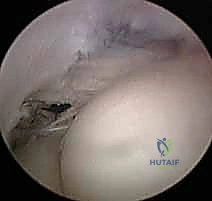

2. جراحة الكوع بالمنظار (Arthroscopic Tennis Elbow Release)

باعتباره رائداً في جراحة مناظير المفاصل في اليمن، يقدم الدكتور هطيف خيار الجراحة بالمنظار (بتقنية 4K عالية الدقة).

مميزات المنظار: